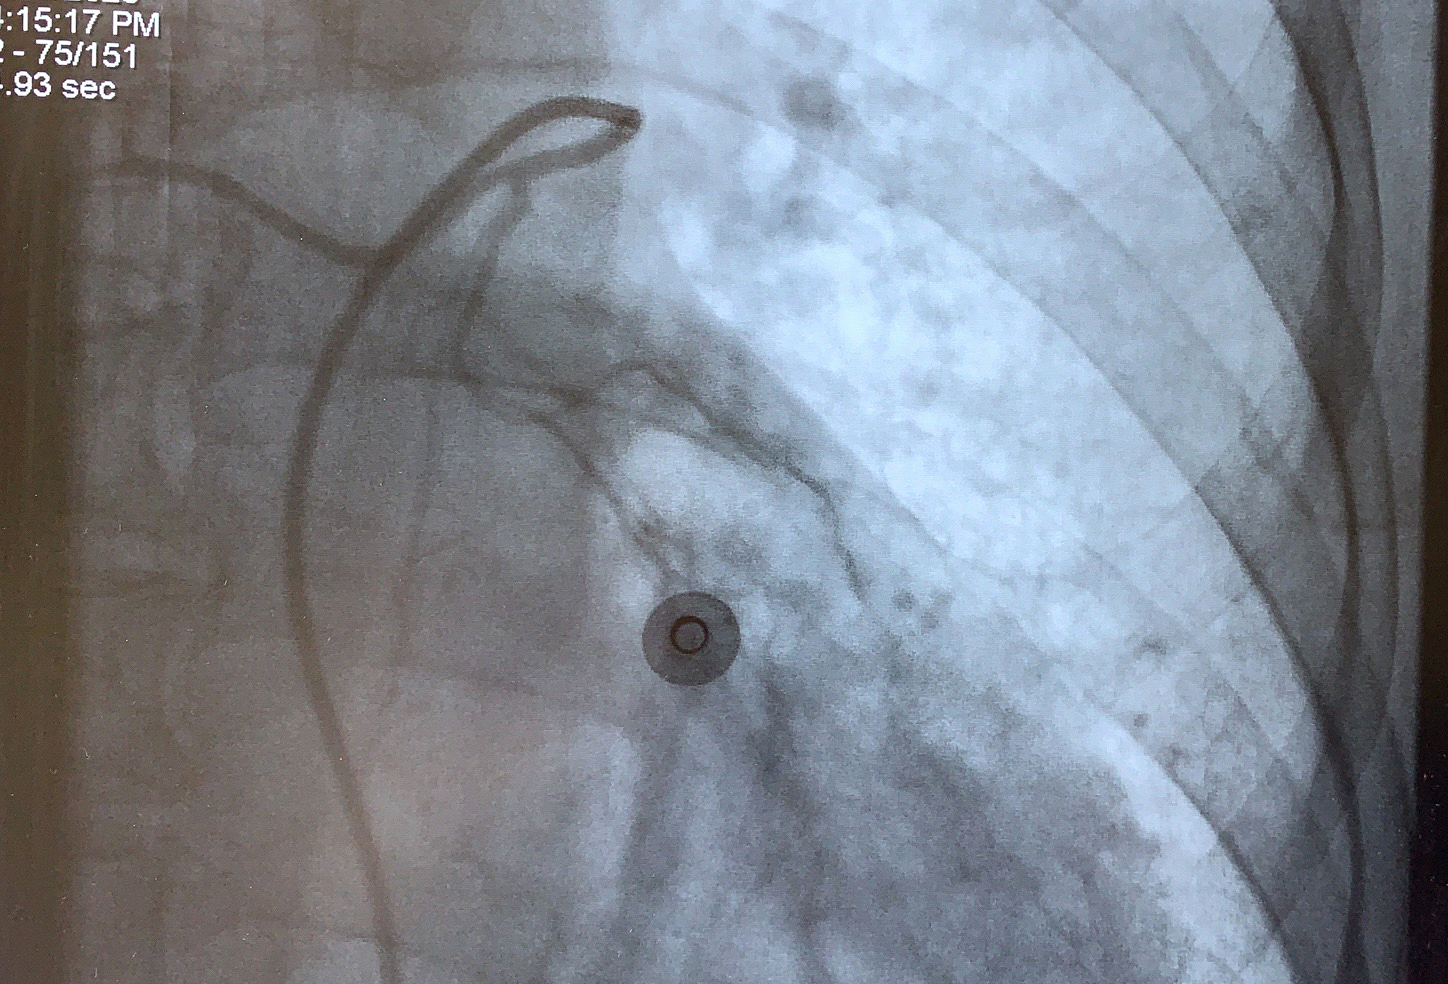

患者被送入介入治疗室,术中造影发现双侧支气管动脉细小分支均破裂出血,予以选择进入后栓塞血管床,栓塞完后造影支气管动脉远端未见显影。术后患者未再咯血,无特殊不适,无并发症,手术成功。